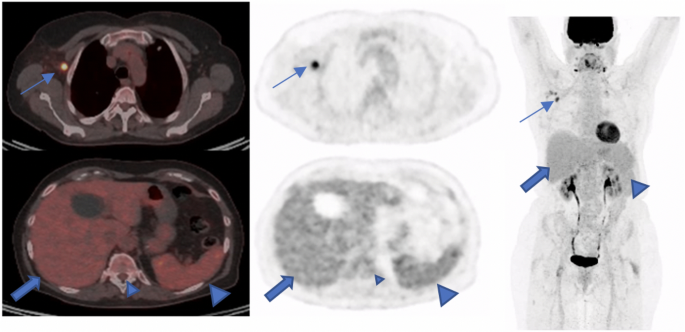

Our study also showed the metabolic changes in lymph nodes and reference regions in a group of patients with pre-vaccination PET/CT examinations. In this patient population, we observed a significant change of metabolic activity in axillary lymph nodes and the liver. It shows the importance of knowledge of physiological and/or pathological changes of immune response after vaccination in the field of Nuclear Medicine. It is also shown in other studies that diffuse 2-[18F] FDG-activity can be seen in the spleen as a result of immune response after COVID-vaccination30 Figure 3.

A 73-old woman with a suspicious lung nodule was referred to our division for F18-FDG PET/CT examination. She was vaccinated 4 days before PET/CT. The lung nodule did not show any pathological FDG-Uptake; however, high tracer activity was detected on her right arm, where she was injected, and multiple hypermetabolic lymph nodes in the right axilla (arrows). Moreover, PET/CT showed high tracer activity in the liver (black arrows), spleen (triangular arrows), and bone marrow (small triangular arrows) as the result of systemic immune response after vaccination. The tracer defect in the liver was due to the known cyst. (A) fusion scan, (B) PET, (C) maximum intensity projection.